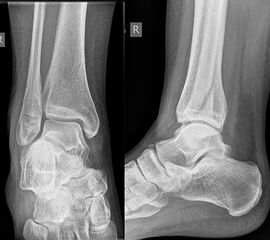

Die Standard-Röntgenaufnahmen des oberen Sprunggelenks bestehen aus drei Aufnahmen: der antero-posterioren Aufnahme (ap), der antero-posterioren Aufnahme mit Innenrotation des Unterschenkels von 20° („Mortise view“), sowie der streng seitlichen Aufnahme (siehe S2-Leitlinie Sprunggelenksfraktur). In der Röntgen-Bildgebung sollte neben den klassischen Frakturzeichen die Integrität der Syndesmose beurteilt werden. Dies erfolgt über die Beurteilung der Breite des lateralen und medialen Gelenkspalts („medial clear space“), des tibiofibularen Abstands 1cm oberhalb des OSG-Gelenkspalts („tibiofibular clear space“), bzw. der tibiofibularen Überlappung. Eine Verbreiterung des tibiofibularen Abstands über 5 mm oder die Erweiterung des medialen Gelenkspalts können Zeichen einer begleitenden Syndesmosenverletzung sein. (Abbildung 3) 6.

Liegt eine Fraktur des oberen Sprunggelenks vor, ist sowohl zur Entscheidung für ein konservatives oder operatives Vorgehen, als auch zur Operationsplanung, ein ausreichendes Verständnis der Fraktur und ihrer Morphologie notwendig. Insbesondere bei komplexen Verletzungen ist dafür die konventionelle Röntgenaufnahme in vielen Fällen nicht ausreichend. So konnten z.B. Black et al. zeigen, dass die operative Strategie zur Versorgung von OSG-Frakturen in 24% basierend auf einer zusätzlichen CT-Bildgebung relevant geändert wurden 7. Dies betraf die Lagerung, die Wahl des Zuganges und die Art der osteosynthetischen Versorgung. Besonders häufig änderte sich das Vorgehen bei Verletzungen des medialen (21%) und des posterioren Malleolus (15%). Darüber hinaus führten dislozierte (dislozierte Frakturen 31% vs. nicht-dislozierte Frakturen 20%) oder komplexe Frakturen (Trimalleolar-Frakturen 29% vs. Unimalleolar-Frakturen 10%) besonders häufig zu relevanten Änderungen des operativen Vorgehens. Die Computertomographie ist daher, insbesondere bei Bi- und Trimalleolar-Frakturen, essentiell für das Verständnis der Fraktur und somit für die Planung und Durchführung der Operation. In Abbildung 4 und 5 sind exemplarisch ein Röntgen- und ein CT Befund gegenübergestellt.